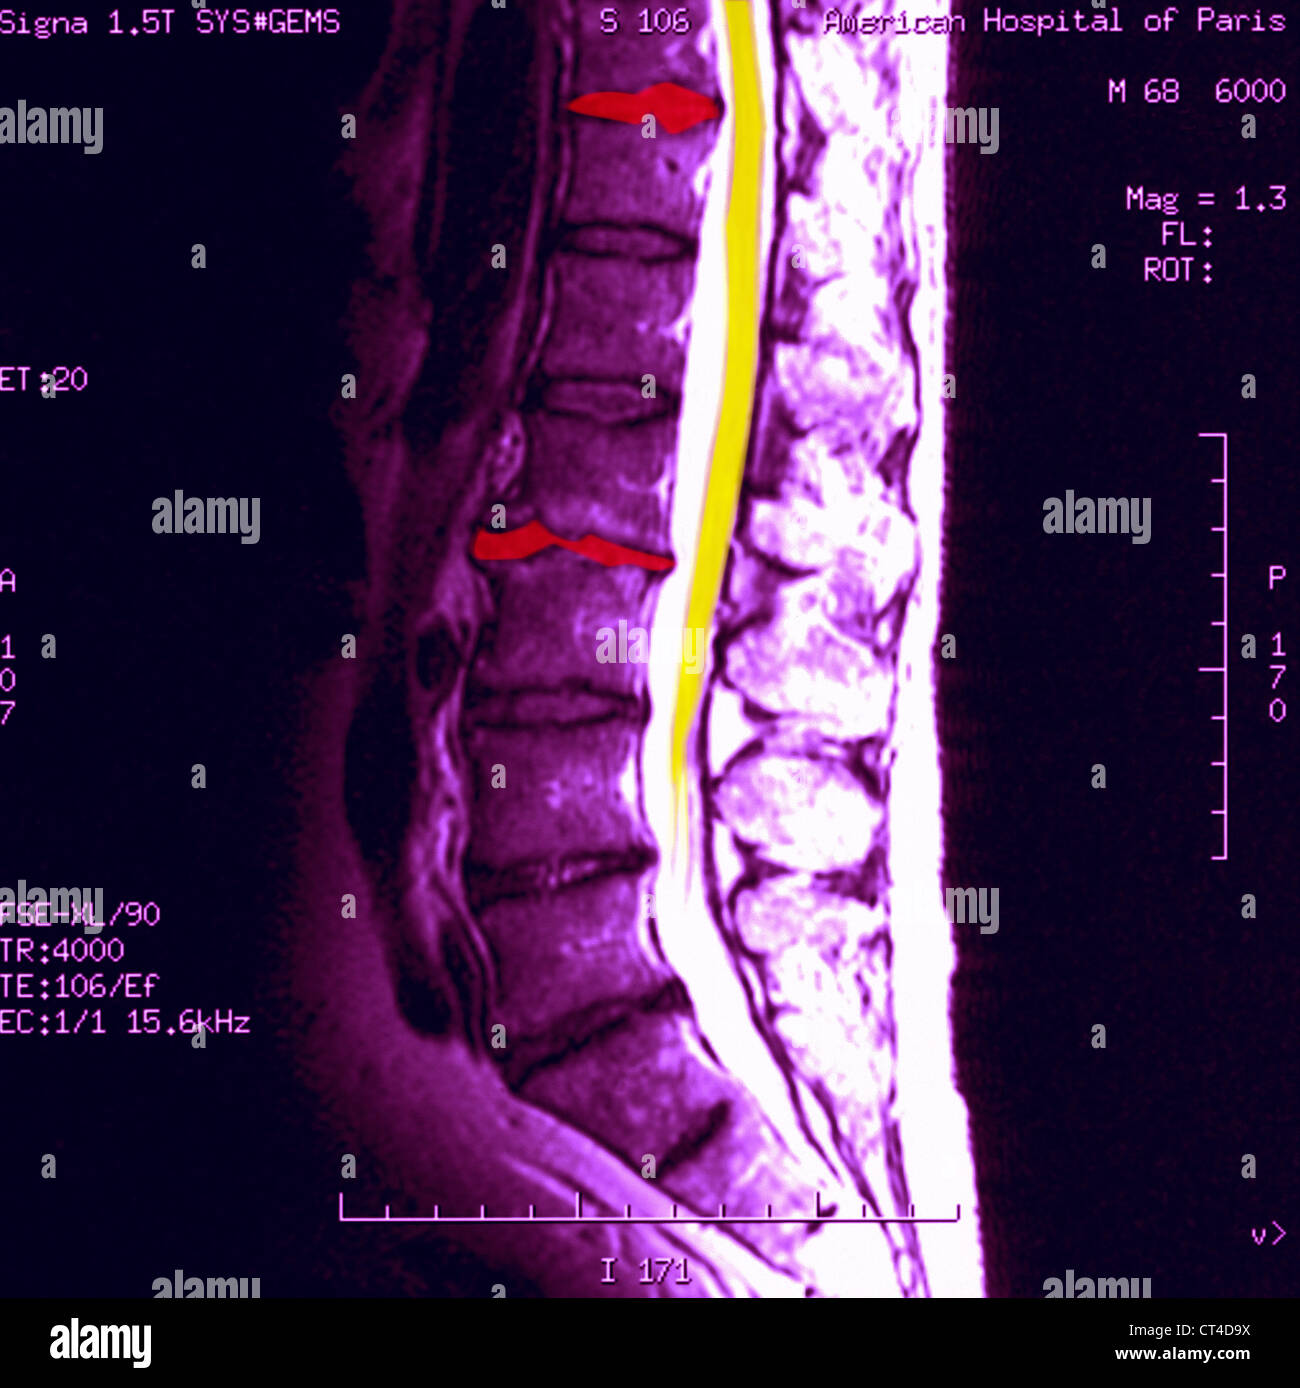

Vertebral Disc Mri. magnet resonance imaging (mri) is the most commonly used imaging modality for diagnosis of degenerative disc disease (ddd). Lack of precise observations and.  — among imaging methods, magnetic resonance imaging (mri) is the most frequently used modality for the.  — desiccated disc refers to a disc with reduced water content, predominantly of nuclear tissues. lumbar spine mri annotation with intervertebral disc height and pfirrmann grade predictions degeneration of the intervertebral discs of the spine is a very common phenomenon in adults which may or may not be symptomatic. The lumbar and cervical spine are most commonly affected.  — disc herniation is displacement of disc material like nucleus pulposus, parts of the annulus fibrosus and cartilage, beyond the. The vertebral body endplate surfaces may become sclerotic (whiter than normal), thickened and irregular.  — on mri, these pathologic changes correspond most commonly to areas of increased.

lumbar spine mri annotation with intervertebral disc height and pfirrmann grade predictions  — disc herniation is displacement of disc material like nucleus pulposus, parts of the annulus fibrosus and cartilage, beyond the. The vertebral body endplate surfaces may become sclerotic (whiter than normal), thickened and irregular.  — on mri, these pathologic changes correspond most commonly to areas of increased. magnet resonance imaging (mri) is the most commonly used imaging modality for diagnosis of degenerative disc disease (ddd).  — among imaging methods, magnetic resonance imaging (mri) is the most frequently used modality for the. The lumbar and cervical spine are most commonly affected. Lack of precise observations and.  — desiccated disc refers to a disc with reduced water content, predominantly of nuclear tissues. degeneration of the intervertebral discs of the spine is a very common phenomenon in adults which may or may not be symptomatic.

Vertebral Disc Mri Lack of precise observations and.  — disc herniation is displacement of disc material like nucleus pulposus, parts of the annulus fibrosus and cartilage, beyond the. lumbar spine mri annotation with intervertebral disc height and pfirrmann grade predictions The lumbar and cervical spine are most commonly affected. magnet resonance imaging (mri) is the most commonly used imaging modality for diagnosis of degenerative disc disease (ddd). degeneration of the intervertebral discs of the spine is a very common phenomenon in adults which may or may not be symptomatic.  — desiccated disc refers to a disc with reduced water content, predominantly of nuclear tissues. Lack of precise observations and.  — on mri, these pathologic changes correspond most commonly to areas of increased. The vertebral body endplate surfaces may become sclerotic (whiter than normal), thickened and irregular.  — among imaging methods, magnetic resonance imaging (mri) is the most frequently used modality for the.